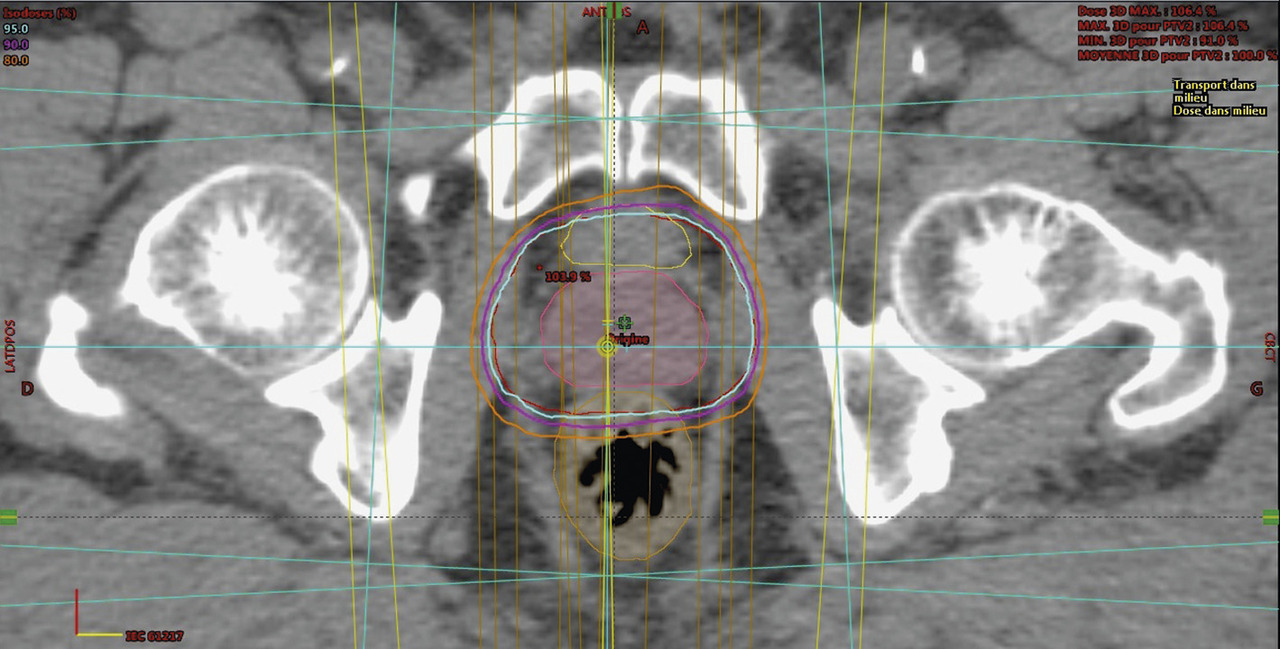

La technique 3D (ou conformationnelle) a bénéficié d’une part de l’arrivée du scanner dans les services de radio­thérapie, d’autre part des progrès de l’informatique, permettant de reconstruire en 3D les volumes souhaités et de donner également une dosimétrie plus précise pour chacun de ces volumes (fig. 1). Il était alors possible de visualiser et donc de délinéer (tracer le contour de) non seulement la prostate, mais aussi les OAR. Parallèlement, le développement des collimateurs multilames (fig. 2) permettait de sculpter le volume prostatique avec une précision quasi millimétrique. La radiothérapie 3D a clairement permis de diminuer la toxicité rectale et urinaire.

Pour que la dosimétrie soit encore plus précise, la fluence particulaire (nombre de photons par unité de surface du champ par seconde) doit être modifiée, pour que les zones ne devant recevoir qu’une faible dose soient épargnées. Ceci a été rendu possible par la mobilité des lames pendant l’irradiation, certaines zones étant cachées une partie du temps de traitement. Pour affiner encore la dosimétrie, le logiciel du système de traitement calcule la durée de chaque faisceau et le mouvement des lames, en fonction des contraintes dosimétriques que l’oncologue radiothérapeute demande (dose à délivrer aux volumes-cibles, dose à ne pas dépasser sur les OAR – dosimétrie inverse). Ces évolutions technologiques

caractérisent la RCMI, apparue et diffusée/infusée dans le courant des années 2000.